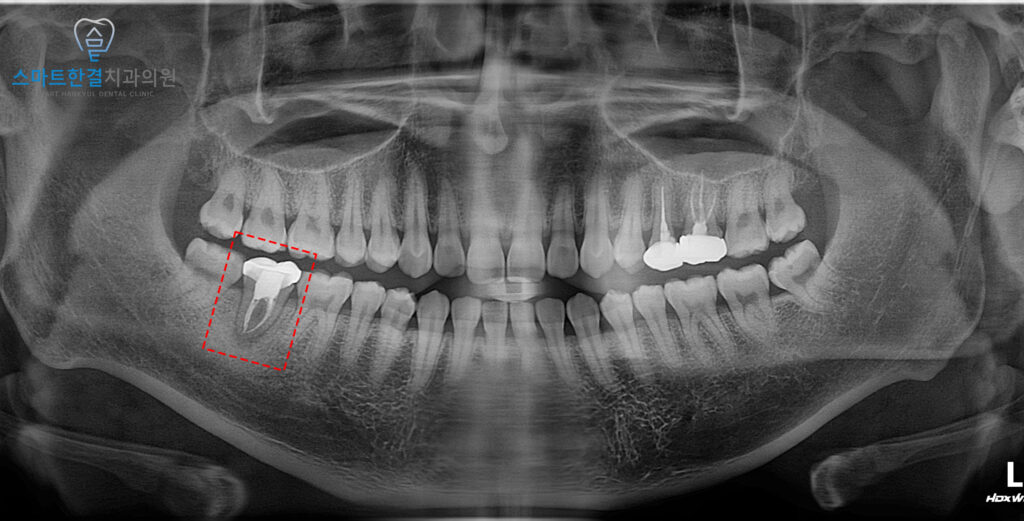

23.10.19

위 환자분께서는

오래전 신경치료를 받았던 치아가

씹을 때 마다 아프고 불편하다며

화서동치과 스마트한결에

내원해 주셨는데요.

겉으로 보기에는 큰 문제가 없어 보였지만,

내부에서 문제가 생겼을 수 있기 때문에

자세히 확인을 해보기로 했어요.

파노라마를 촬영하여 확인해 보니,

신경치료를 받았던 치아 뿌리로

염증이 잡혀있는 것을 확인할 수 있었어요.